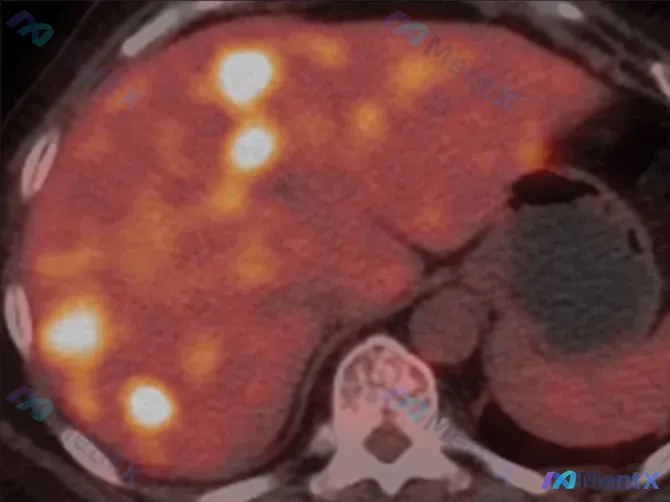

62岁女性偶然发现肝内多发高代谢结节,SUVmax8.8,你会怎么考虑?

看到一个病例资料,整理了一下思路和大家分享。 基本情况 - 患者:62岁女性 - 主诉:偶然发现肝脏多发病变 - 症状:无明显伴随症状(无症状) 关键影像表现(PET-CT) - 肝脏内可见多发、大小不一的局灶性病变 - 代谢特征:FDG高摄取,SUVmax达8.8 - 分布:散在于肝脏不同叶段 -...